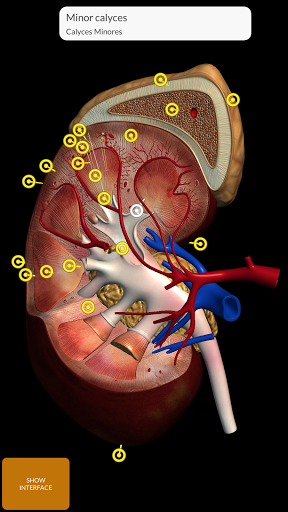

يتيح لك "Anatomy 3D Atlas" دراسة التشريح البشري بطريقة سهلة وتفاعلية.

من خلال واجهة بسيطة وبديهية، من الممكن ملاحظة كل بنية تشريحية من أي زاوية.

تتميز النماذج التشريحية ثلاثية الأبعاد بتفاصيل خاصة ودقة تصل إلى 4K.

نماذج تشريحية ثلاثية الأبعاد

• الجهاز البولي التناسلي (للذكور والإناث)